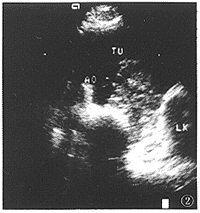

X線檢查3.B型超聲檢查:亦可發現後腹膜腫瘤和腫大的淋巴結,但腸內氣體干擾使診斷很難精確,而對腹主動脈瘤的診斷或排除較為可靠。在B型超聲引導下活檢或隨訪腫瘤化療後的變化很有參考意義,單獨超音波檢查常不易將後腹膜腫瘤與膿腫或血腫區分,囊性腫瘤易與寄蟲囊腫、炎性或創傷性血腫相混淆。在B型超聲或CT引導下經皮細針吸引力活檢對診斷有較大意義,確診率達80%左右。

原發性腹膜後腫瘤--B超片一、手術原則1.由於腹膜後腫瘤來源豐富,種類繁多,解剖複雜,故應術前做好充分準備。2.手術切除力爭完全徹底,減少復發率。3.有鄰近臟器受侵或術後復發者,可行腫瘤及受累臟器聯合切除。曾有報導一例復發性脂肪肉瘤患者,第三次手術行腫瘤及左腎、脾、左半結腸和部分小腸聯合切除,現已9年無復發。4.對於腫瘤侵犯周圍臟器及較大血管而不能理想切除時,可行姑息性切除或腫瘤減量切除術。5.惡性腫瘤切除術後,應輔以化療、放療或/和免疫等綜合療法。